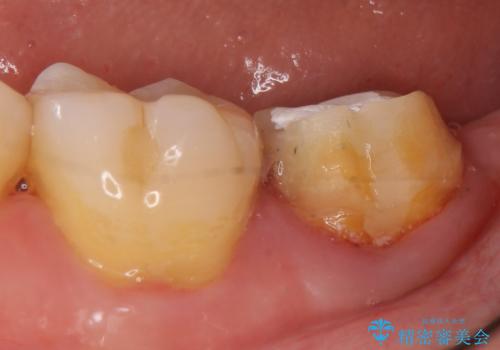

- 他院にて根管治療を行っていたが、痛みが引かないため当院での診療を希望された方の症例です。

改めて再根管治療を行い、症状の緩解を確認後、オールセラミッククラウンによる補綴を行いました。